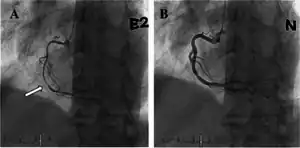

a) Occlusion of mid portion of right coronary artery b) after injection of intracoronary nitrate shows resolution

Although variant angina has been documented in between 2% to 10% of people with angina, it can be overlooked after ruling out typical angina. Individuals who develop cardiac chest pain are generally treated empirically as an acute coronary syndrome, and are immediately tested for elevations in their blood levels of enzymes such as troponin that are markers for cardiac damage. They are also tested by ECG which may suggest variant angina if it shows elevations in the ST segment or an elevated ST segment plus a widening of the R wave during symptoms that are triggered by a provocative agent (e.g. ergonovine or acetylcholine). The electrocardiogram may show depressions rather than elevations in ST segments but in all diagnosable cases clinical symptoms should be promptly relieved and ECG changes should be promptly reversed by rapidly acting sublingual or intravenous nitroglycerin. However, the gold standard for diagnosing variant angina is to visualize coronary arteries by angiography before and after injection of a provocative agent such as ergonovine, methylergonovine or acetylcholine to precipitate an attack of vasospasm. A positive test to these inducing agents is defined as a ≥90% (some experts require lesser, e.g. ≥70%) constriction of involved arteries. Typically, these constrictions are fully reversed by rapidly acting nitroglycerin.[4][16]